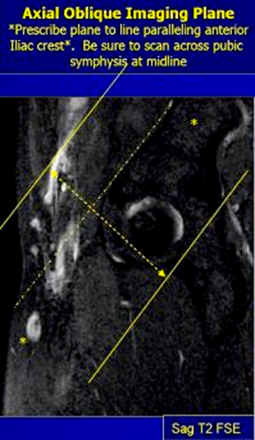

AX OBL PD (TE=20msec) TSE 3-4 mm 0.5-1mm None 20cm Parallel anterior iliac crest, from crest thru hip joint

AX OBL T2 SPAIR TSE 3-4 mm 0.5-1mm SPAIR 20cm Parallel anterior iliac crest, from crest thru hip joint

MRI Pelvis Sports Hernia WO MSK Protocol image 4